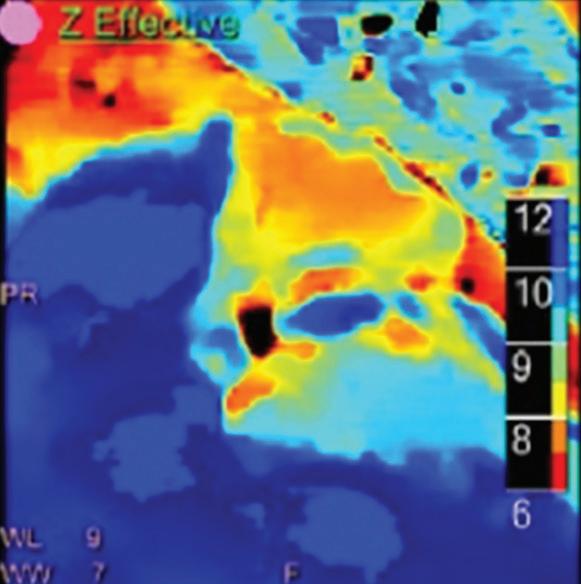

Z Effective (Zeff)

Effective atomic number. Each voxel is set to a value in the range 5 to 30 representing the effective atomic number of that voxel. Z effective of air is set to zero. For reference, Z effective of water is 7.4, Z effective of cortical bone is 13.2, and Z effective of fat is 5.9. Z effective maps are very sensitive to materials characteristics (Figure 3) and can also be used to display perfusion maps and to identify very subtle perfusion deficits (Figure 2b). The accuracy measured on a Gammex phantom with iodine, calcium, and soft tissue inserts show that the majority of Z effective values are within 0.2 Z effective units and are consistent between 120 and 140 kVp scans.21